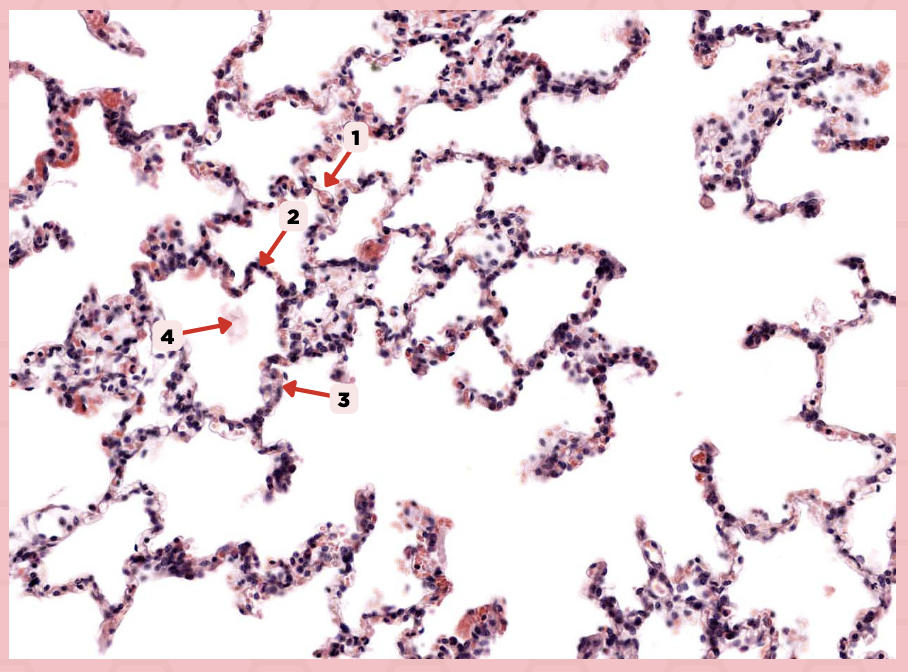

Interalveolar septum

Identify the structure labeled as 1.

Type I alveolar cell

Identify the structure labeled as 2.

Type II alveolar cell

Identify the structure labeled as 3.

Pulmonary Alveolar Macrophages (Dust Cells)

Identify the structure labeled as 4.

Pulmonary Alveolar Macrophages (Dust Cells)

What are the most numerous cells inside the alveoli?

Pneumocyte Type I

Which of the following labeled structures covers 95% of the alveolar surface?

Type I alveolar cell

Identify the structure labeled as 1.

Type II alveolar cell

Identify the structure labeled as 2.

Pulmonary Alveolar Macrophages (Dust Cells)

Identify the structure labeled as 3.

Endothelial Cells

Identify the structure labeled as 4.